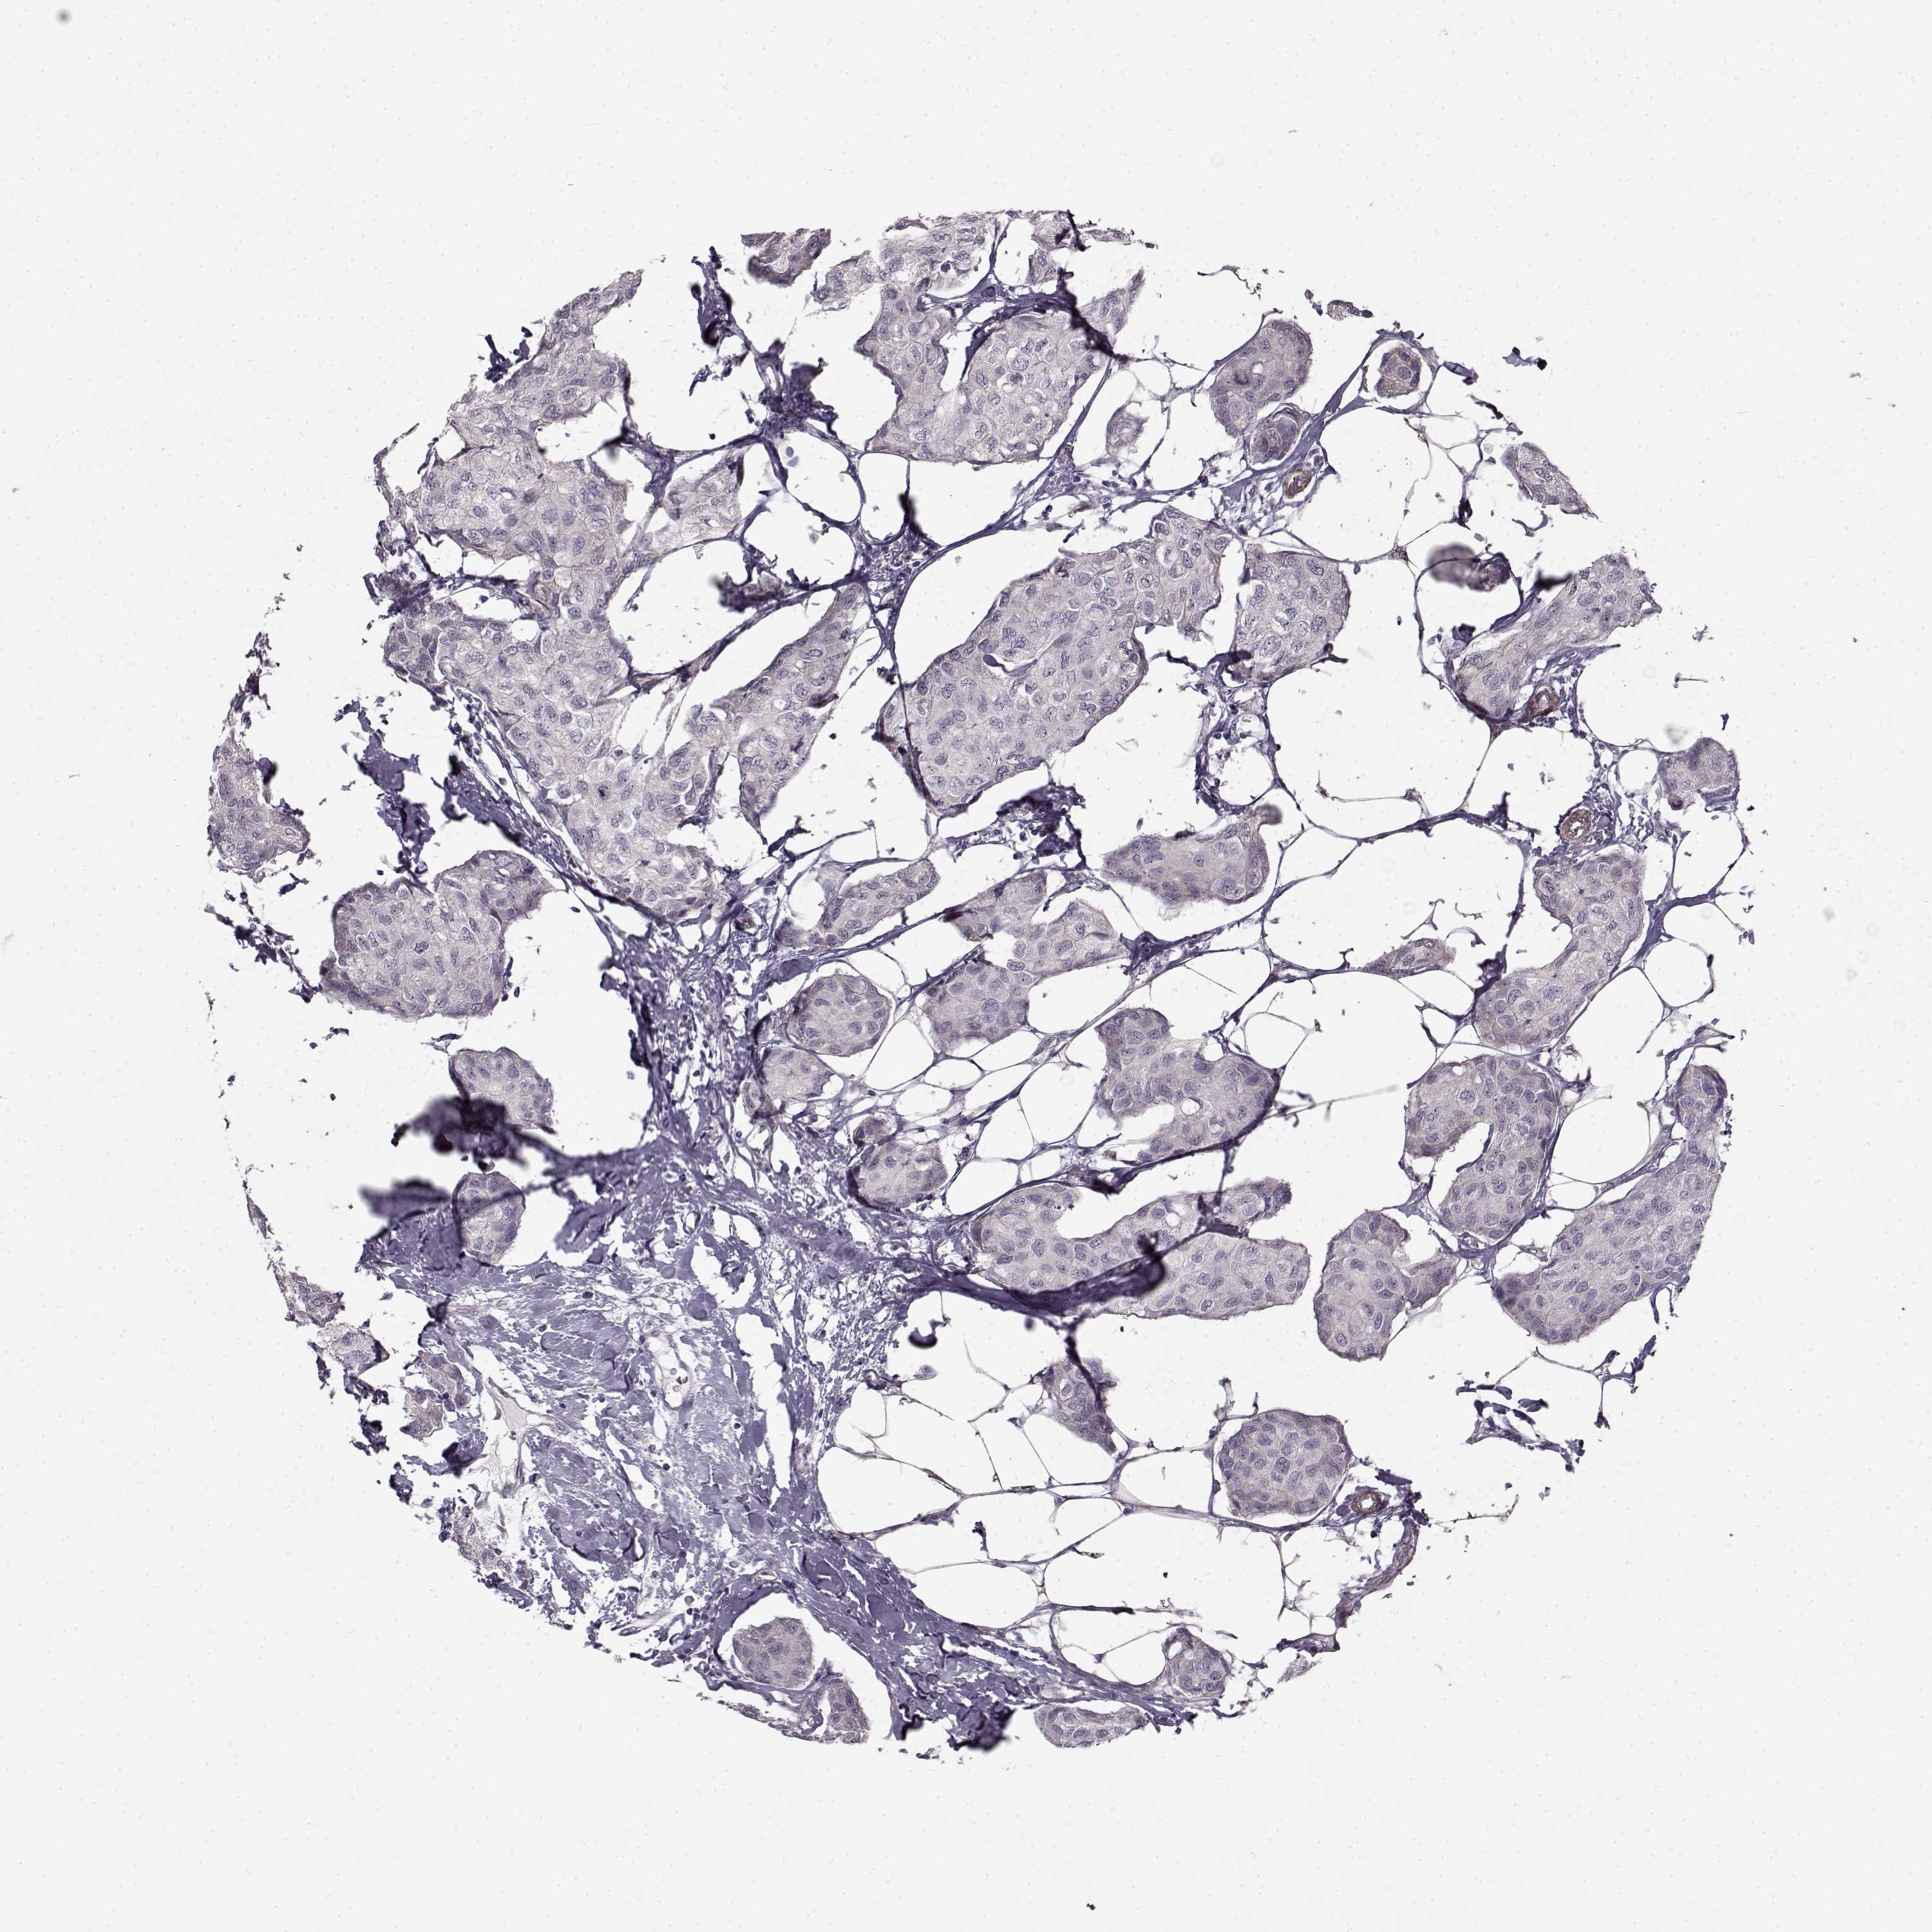

CANCER BREAST CANCER Show tissue menu

BRCA TCGA BRCA VALIDATION PROTEIN EXPRESSION

ANTIBODIES

AND

VALIDATION